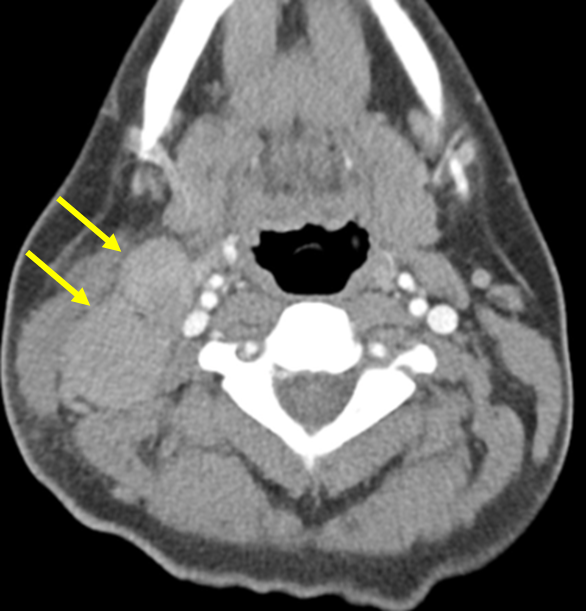

Img | CXR: Mediastinal mass CT: Multiple enlarged Rt. cervical lymph nodes |

• CXR에서 mediastinal mass가 보이며 neck CT에서 Rt. cervical lymphadenopathy가 확인된다. Mediastinal mass는 lymphoma가 mediastinal LN에도 존재하는 것을 시사한다.